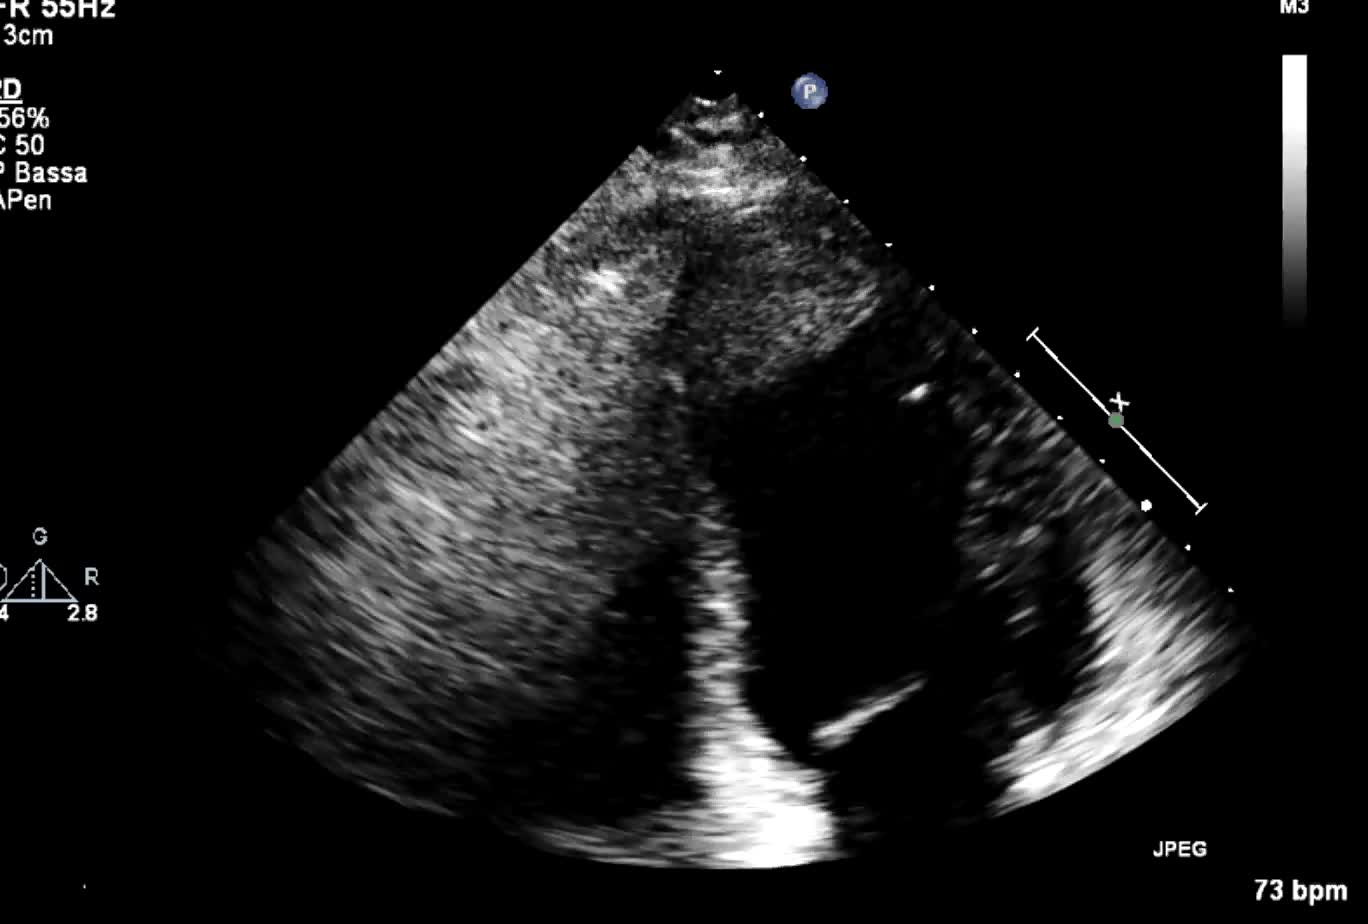

Trombosi apice VS

Autore:

Daniela Torta